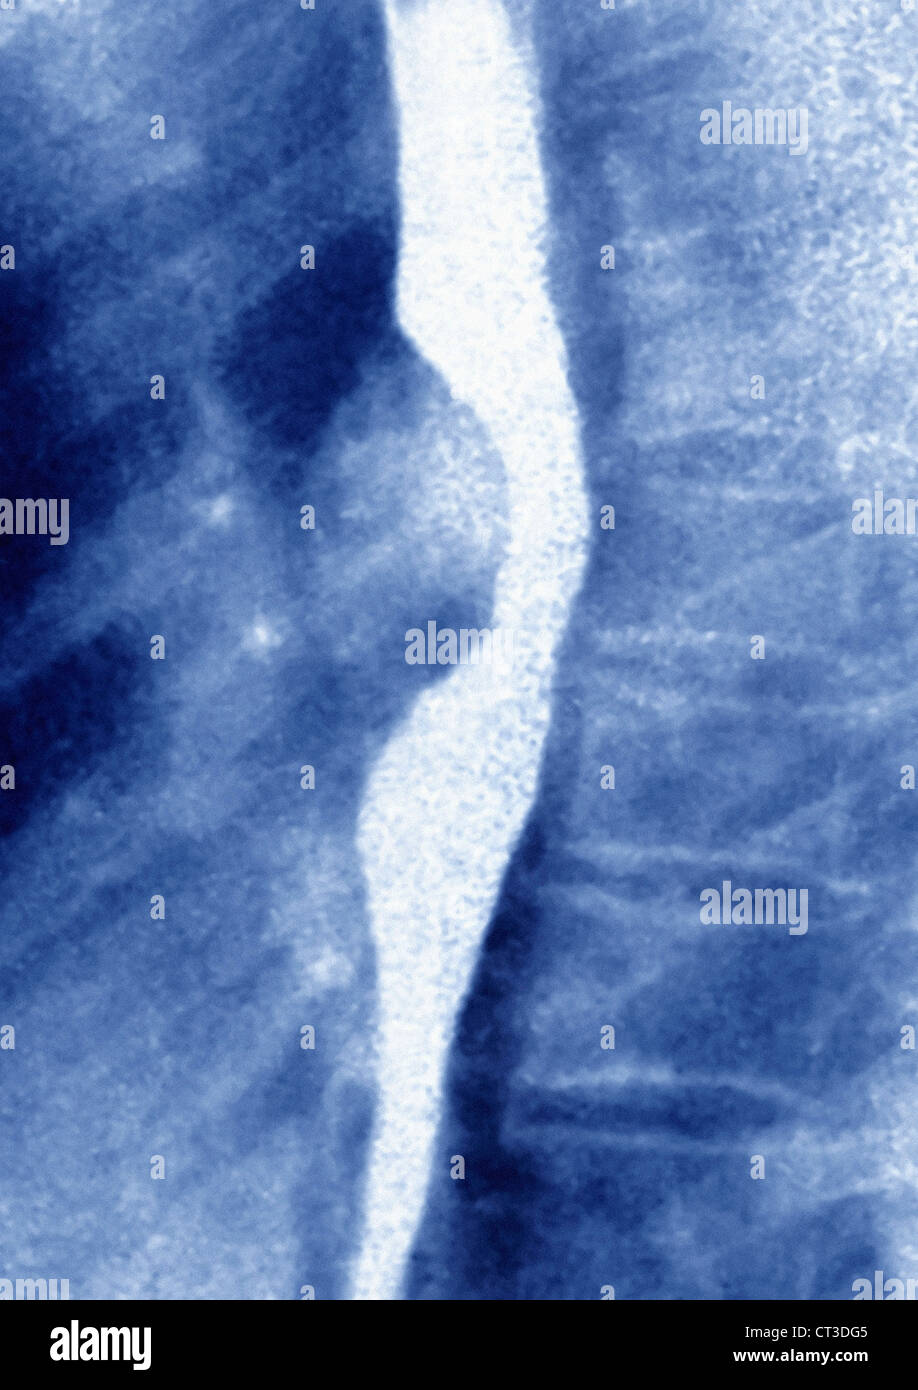

From www.alamy.com

ESOPHAGEAL LEIOMYOMA, XRAY Stock Photo Alamy What Is Esophageal Leiomyoma It is the most common benign tumor. endoscopic ultrasonography is the most accurate method in diagnosis of esophageal leiomyoma. esophageal leiomyoma is a very rare tumor that arises from mesenchymal tissue. leiomyomas are benign tumors of smooth muscle origin that are most commonly seen in the uterus. Asymptomatic or smaller lesions should be followed periodically with barium. What Is Esophageal Leiomyoma.